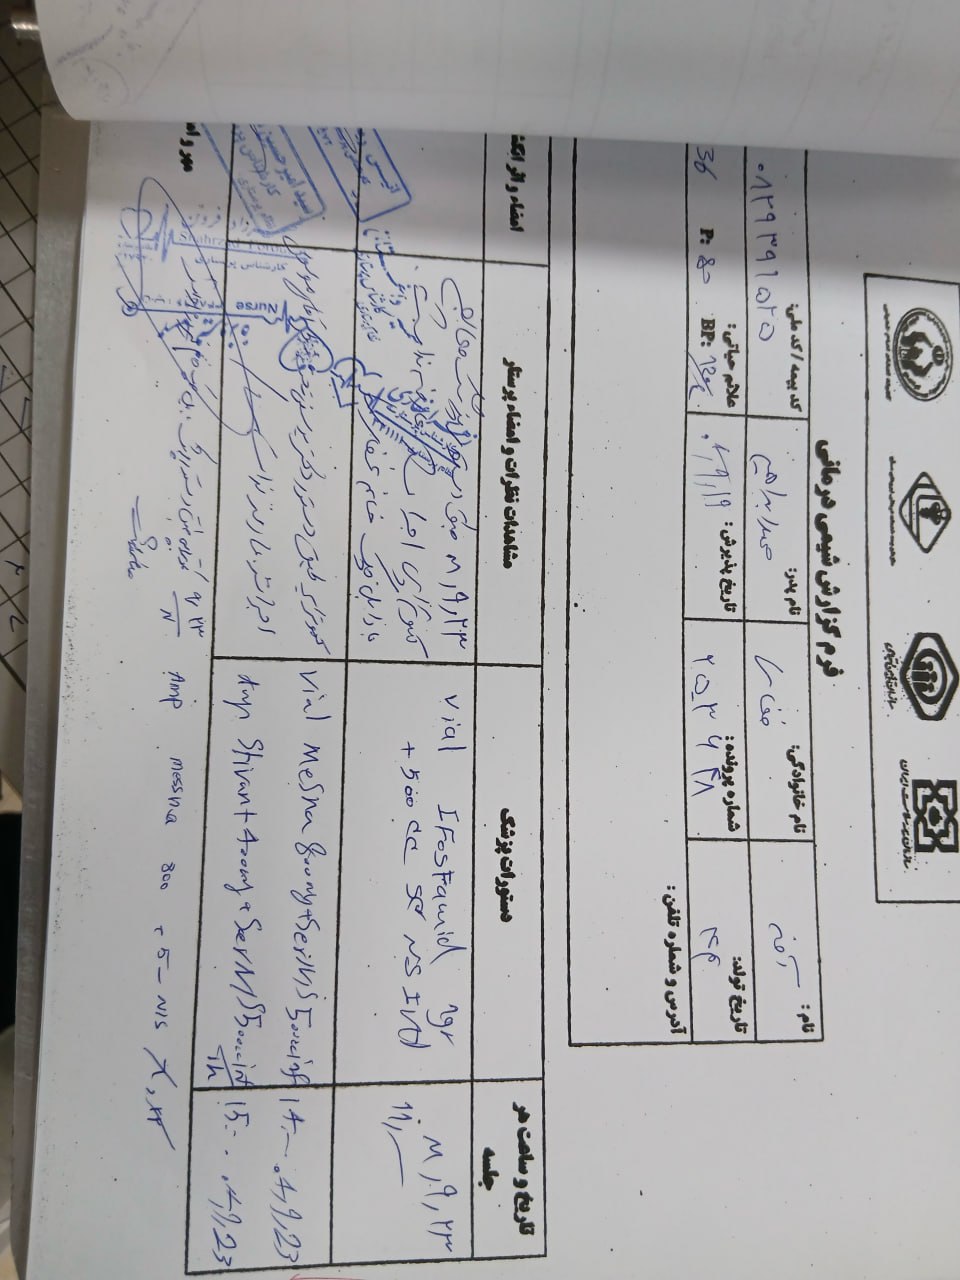

(تصویر مربوط به این مراجعه نیست) Other:

(تصویر مربوط به این مراجعه نیست) Other:

(تصویر مربوط به این مراجعه نیست) Other:

(تصویر مربوط به این مراجعه نیست) Other:

به ترتیب؛ روز ها: ۱۹ آبان, ۲۸ آذر, ۲۹ آذر, ۳۰ آذر

به ترتیب؛ روز ها: ۱۹ آبان, ۲۸ آذر, ۲۹ آذر, ۳۰ آذر

۱۹ آذر

۱۹ آذر

به ترتیب؛ روز ها: ۲۸ آذر, ۲۹ آذر, ۳۰ آذر, ۱ دی

۱ دی